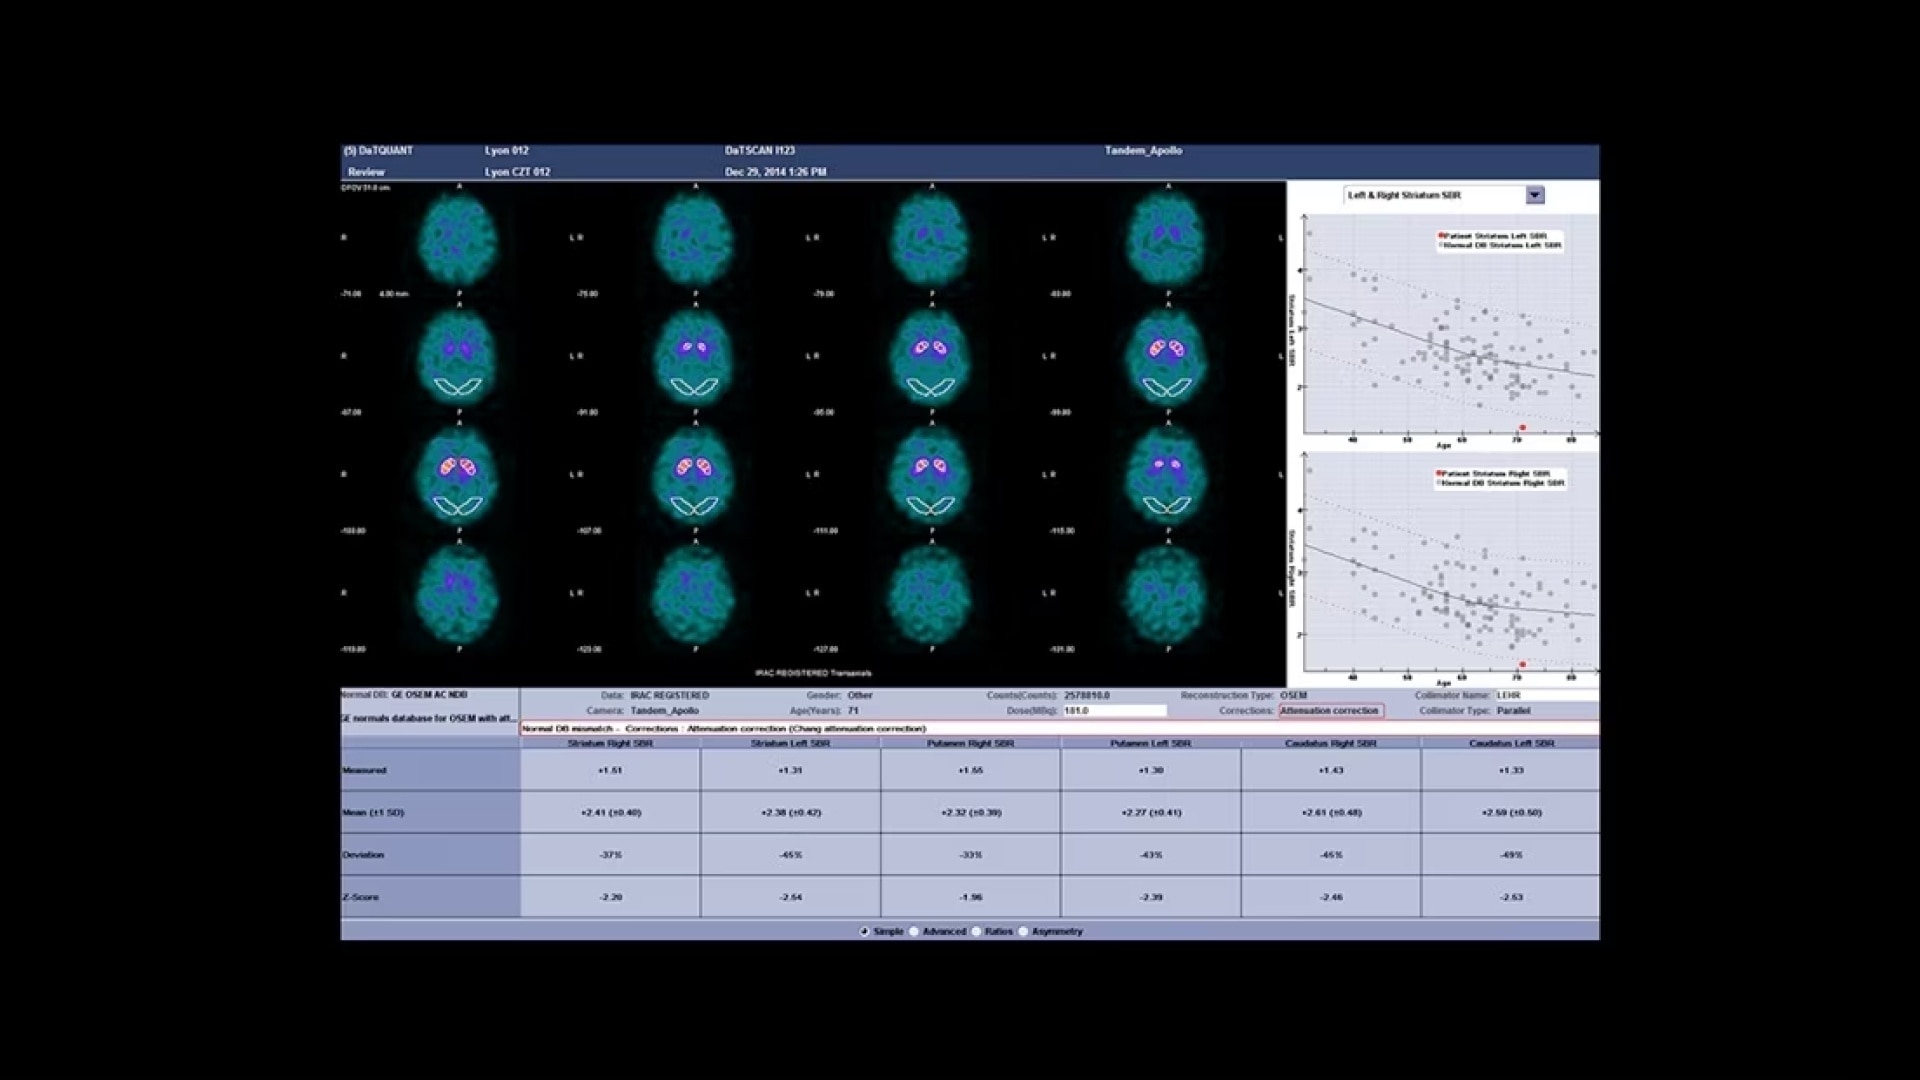

A fully digital vision for nuclear medicine

A fully digital vision for nuclear medicine

Additionally, this is a premium SPECT/CT system that delivers the added flexibility of a standalone CT that includes advancements in dose and metal artifact reduction. And it delivers the accurate, reproducible results referring physicians require in a comfortable and streamlined exam experience.